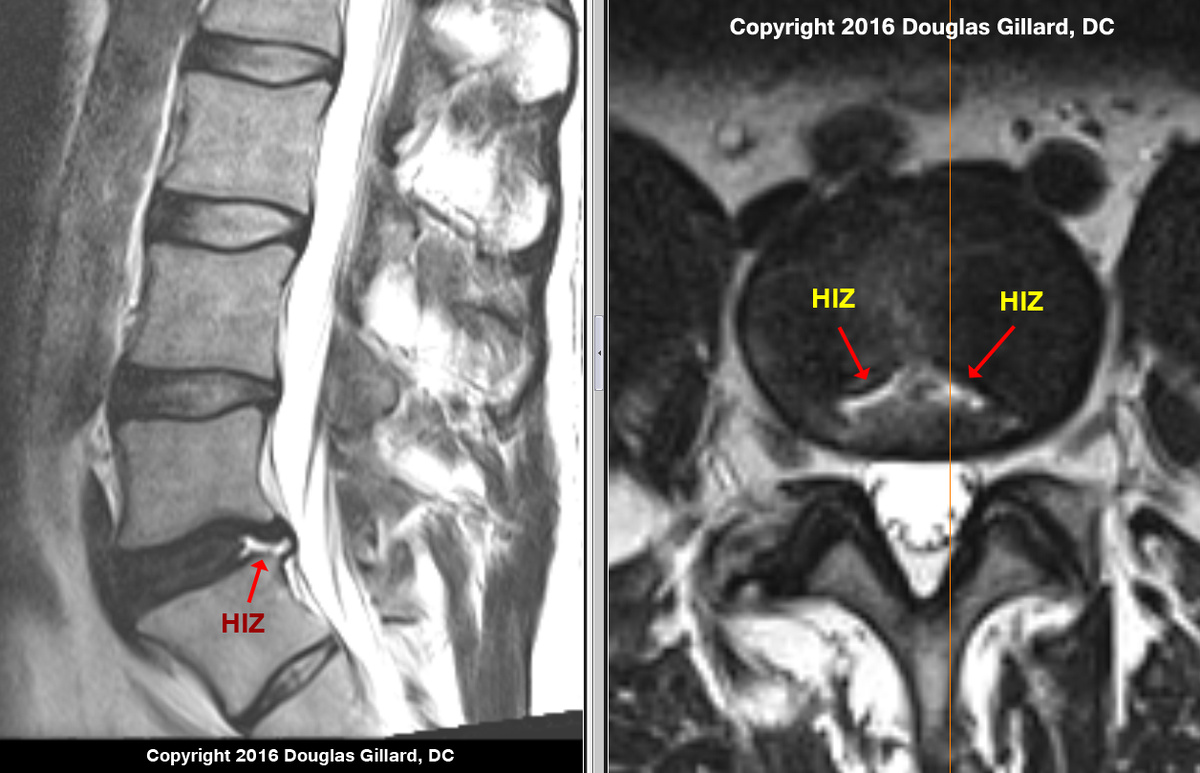

Высокоинтенсивные включения в межпозвонковый диск HIZ

Высокоинтенсивные зоны (HIZ) представляют собой важный диагностический признак, выявляемый при проведении магнитно-резонансной томографии (МРТ).

Основная характеристика HIZ заключается в их обнаружении на снимках в режиме T2W (T2-взвешенные изображения). Эти зоны являются индикатором повреждения фиброзного кольца межпозвоночного диска, которое играет ключевую роль в поддержании структуры позвоночника.

Клиническая значимость HIZ подтверждается статистикой: в 70% случаев наличие таких зон коррелирует с болевым синдромом у пациентов. Это делает их важным маркером при диагностике.